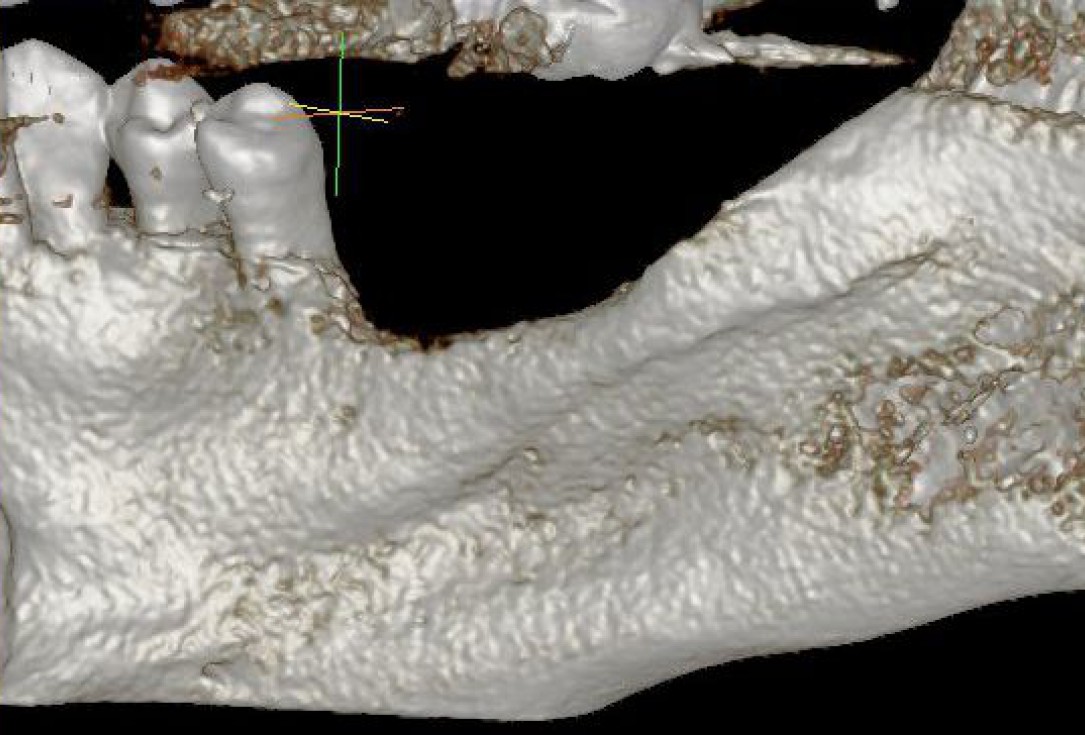

02/28 - Model of the initial defect computed from a CBCT scan - lingual viewThree-dimensional augmentation with maxgraft® cortico - Dr. R. Würdinger